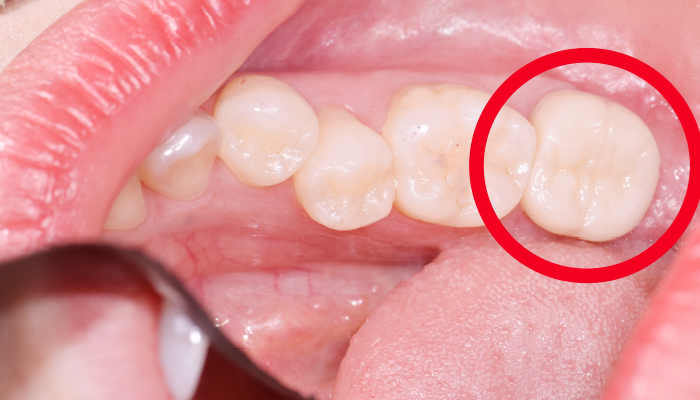

• 치석으로 치아가 많이

착색된 분